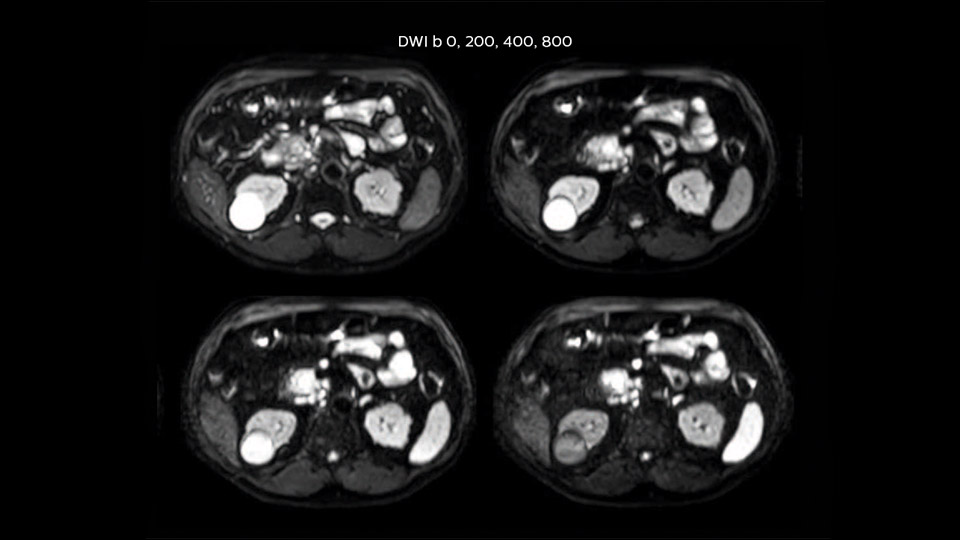

Comparison of liver MRI with and without MultiVane XD motion correction

In this example the image quality of the MultiVane XD images is evidently better than in the images without MultiVane XD. Ingenia 1.5T with dS Torso coil solution.